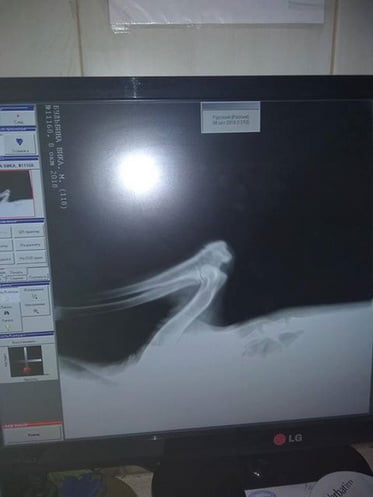

В один день (в субботу, 06.10.2018) в Корабельном районе на проезжей дороге были сбиты 2 собаки: 3-месячный щенок и старая собака.

фото щенка, сделанное Анной буквально за минуты до аварии и после

«В обоих случаях ни один водитель не остановился, чтобы помочь животным, которые остались лежать на дороге!!! Только благодаря зоозащитникам и нескольким небезразличным жителям района у собак есть шанс на ЖИЗНЬ! У них переломы, ЧМТ, лечение только за свой счет и благотворительные перечисления», — рассказала женщина.